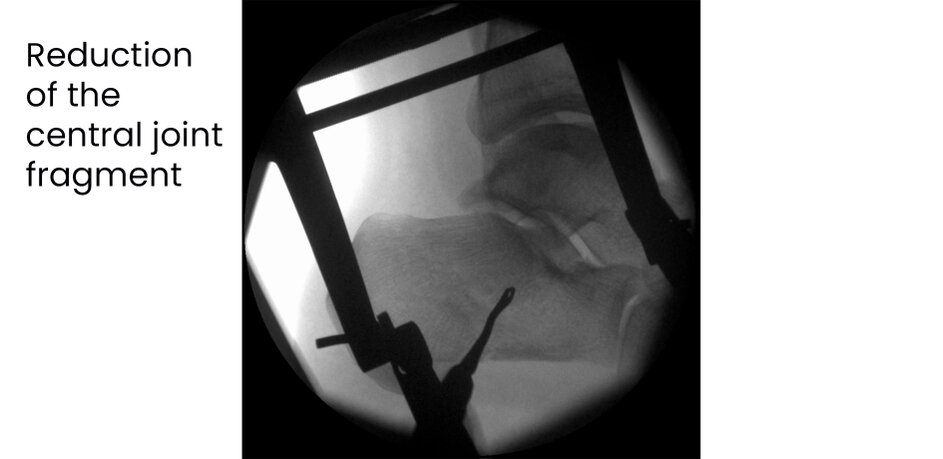

Case 17KL, male, 35y, surgery on day of trauma